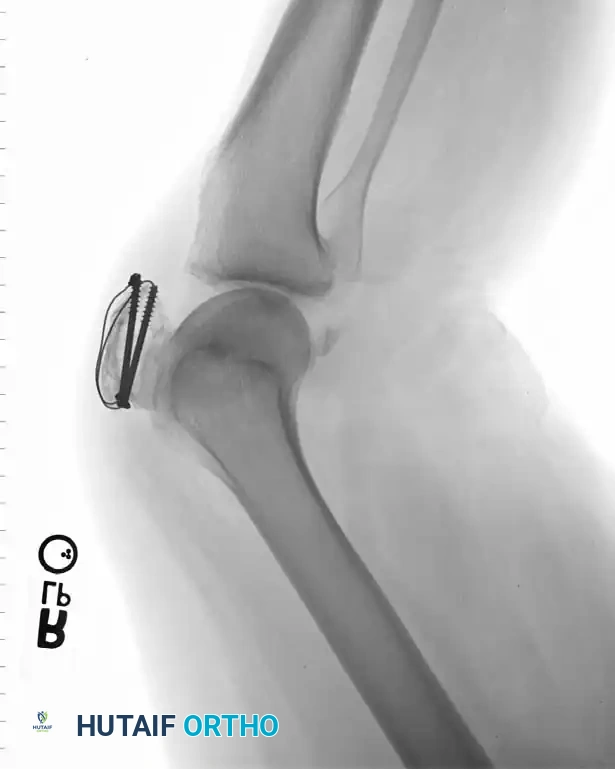

Cannulated Screw Fixation with Tension Band

Recent biomechanical advancements have popularized the use of cannulated screws combined with a tension band wire. Carpenter et al. demonstrated that transverse fractures fixed with a tension band wire passed through parallel cannulated screws failed at the highest load compared to K-wires or screws alone.

Berg described the fixation of displaced transverse fractures using a figure-of-eight wire passed through parallel cannulated compression screws. Advantages of this construct include:

* A low-profile construct that minimizes hardware irritation (a common complication of K-wires backing out).

* Enhanced interfragmentary compression provided by the lag screws.

* Superior biomechanical stability allowing for aggressive early restricted motion.

* Utility as a salvage method following the failure of traditional tension band wiring.

For transverse fractures with large, robust fragments, a tension band modified with cannulated screws is currently the preferred technique. If peripheral comminution is present, a supplemental circumferential cerclage wire can be added.